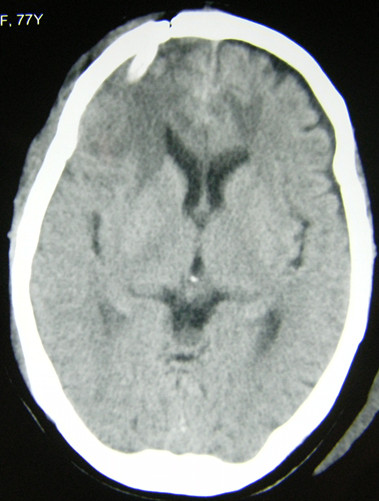

患者女,77岁,因突发头痛、恶心、呕吐并意识不清2小时急诊入院。无高血压病史。查体:浅昏迷状,右侧瞳孔4mm,光反应弱。CT示:右额叶高低密度灶,中线移位。诊断:右额叶脑卒中并脑疝早期。行急症开颅术。

术后2天CT复查:病灶清除良好,中线恢复。患者神志恢复,四肢活动良好。

术后3周CT复查:水肿消退,肿瘤清除彻底。患者已下床活动并出院康复,嘱其定期复查酌情放疗。